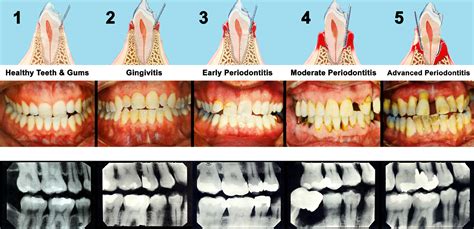

Periodontal disease is a silent, inflammatory condition that affects the tissues surrounding and supporting your teeth. It typically begins as gingivitis, characterized by inflammation, and can advance to periodontitis, which involves the destruction of bone and connective tissue. By examining Gum Disease Pictures, you can often identify the transition from healthy, firm, pink gums to tissues that appear puffy, red, or even receding.

The progression usually follows these stages:

• Gingivitis: The earliest stage where gums are inflamed, sensitive, and prone to bleeding while brushing.

• Early Periodontitis: The gums begin to pull away from the teeth, forming small pockets where bacteria can hide.

• Moderate to Advanced Periodontitis: Deep pockets form, bone support is lost, and teeth may become loose or shift, which is frequently documented in medical Gum Disease Pictures.

• stages of periodontal disease photos